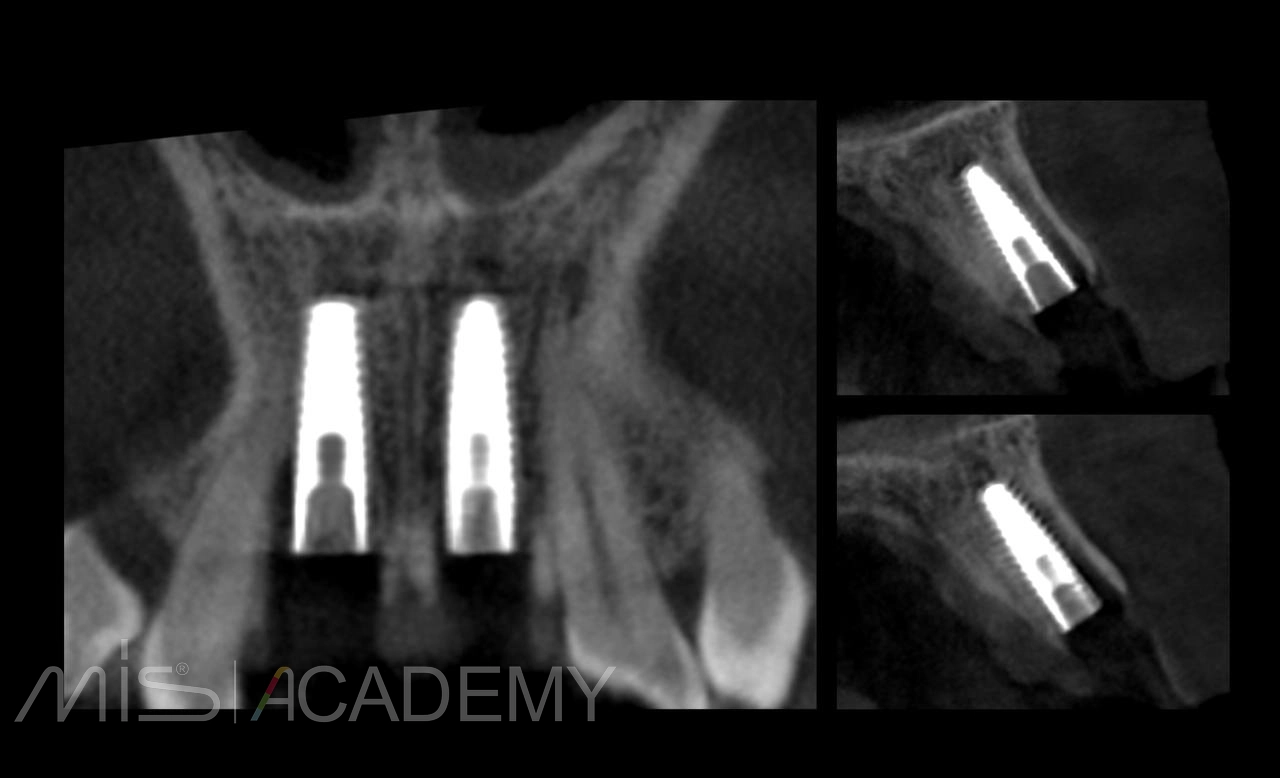

— Установка 2 имплантов MIS C1.

— Постоянное протезирование — через 3 месяца